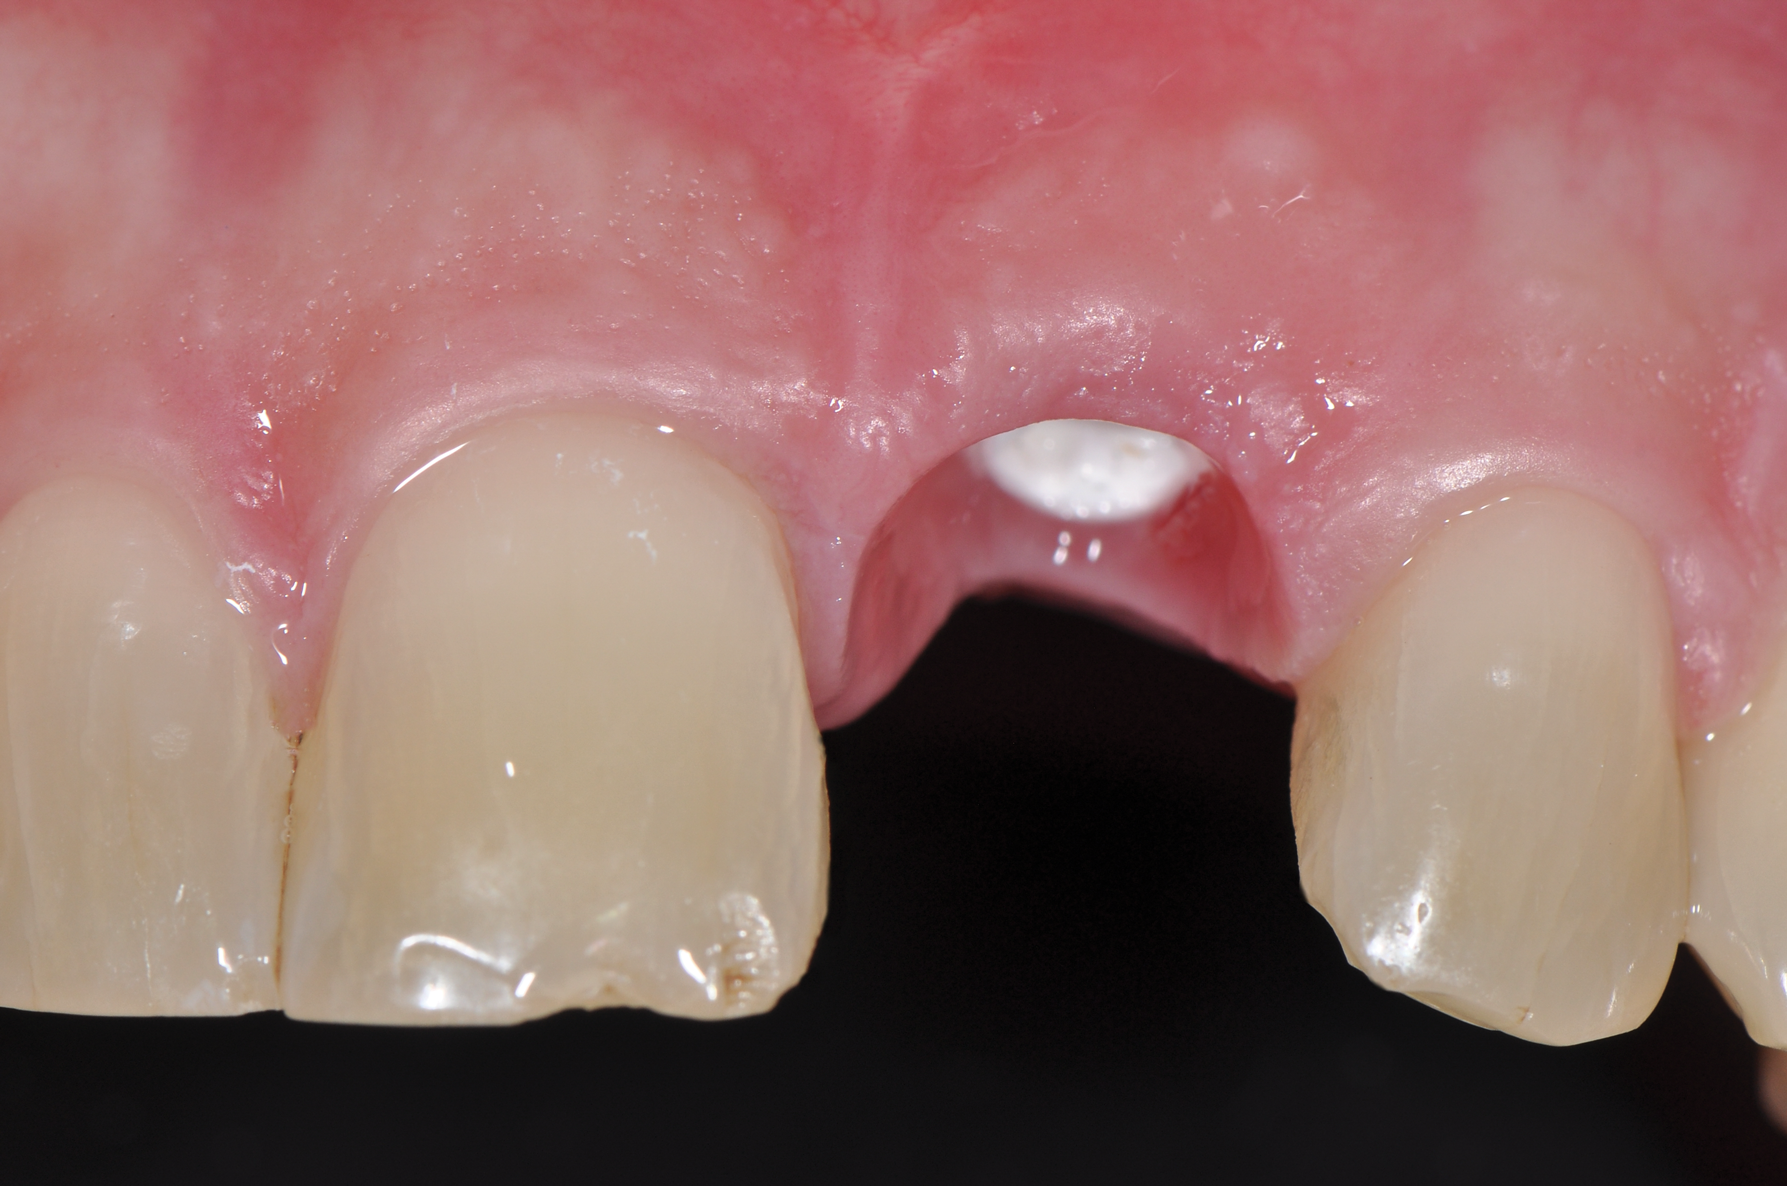

Still, as with titanium implants, undesirable recession with an exposed implant shoulder may occur in rare cases with ceramic implants. Nonetheless, from an esthetic point of view, this inflammation-free recession of the gingiva is likely to be tolerated much better by patients concerned with the dark margins of titanium implants (Figure 2).

Fig 2. Recessions in ceramic (left) and titanium (right) implants.

Figure 2